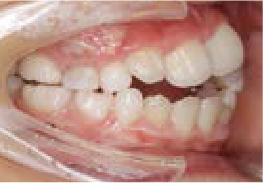

八重歯になっちゃった…歯が入る隙間がないけど、永久歯は抜きたくない!

Aさん (矯正開始時:9歳)

Before

After

すっきりしたお顔立ちの女の子ですが、外側から八重歯が生えてきてしまいました。

治療を終えて

マイオブレイスとBWS装置を使い、あごの骨や歯並びの形を整えながら、鼻呼吸や正しい飲み込み方も身に付けることができました。

お口の悪いクセは改善され、お子さん自身の力でしっかりとしたかみ合わせができるようになりました。ご希望通り永久歯を抜く必要はありませんでした。

主訴・治療内容 他院で「永久歯を抜いて矯正」をすすめられたが抜歯に抵抗があり「永久歯を抜かずに、あごの骨から整えてくれる」と口コミを見て当院を選んでくださいました。

治療期間 2年

費用 495,000円(税込)